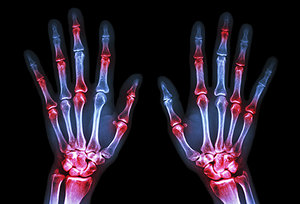

We generally think of arthritis as a disease of aging, although in reality, it can strike anyone, regardless of age, race, gender or occupation. In fact, a recent study not only points out that our youth can be affected by the disease, but also that an all-too-common culprit may be to blame: antibiotic use.

In the study, childhood antibiotic exposure increased the risk of idiopathic (of unknown cause) juvenile arthritis in dose-dependent fashion compared to no exposure. In other words, the more doses of antibiotics received during childhood, the higher the risk of developing arthritis compared to receiving no doses.

arthritis - Copyright – Stock Photo / Register Mark Specifically, any antibiotic use increased the risk by 110 percent, while five or more courses of antibiotics increased the risk by a whopping 200 percent compared to no use. The association between antibiotic use was strongest for exposures within one year of diagnosis.